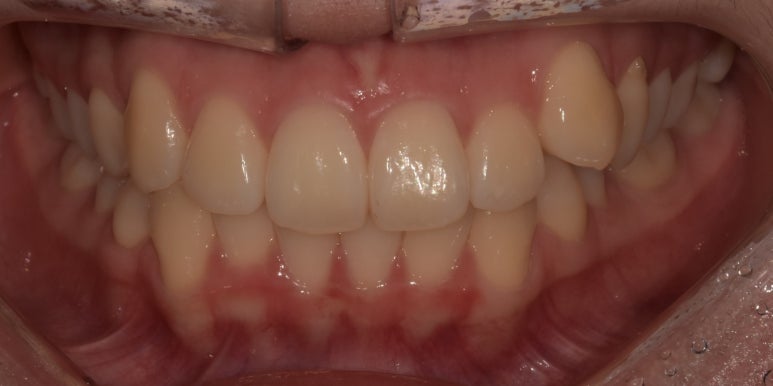

덧니라미네이트 시술 전후

(전) 20241-01-17 (후) 2024-01-24

치료를 마친 모습을 전과 비교해보니 어떤가요?

잇몸라인이 다소 올라가 있는 부분은 어쩔 수 없지만, 앞으로 툭 튀어나와있던 치아가

다른 치아와 유사한 라인으로 맞춰져 더 가지런해 보이죠?

보시면 라미네이트 한 치아와 다른 치아의 색상 또한 큰 차이가 없는 것이 느껴지시죠?